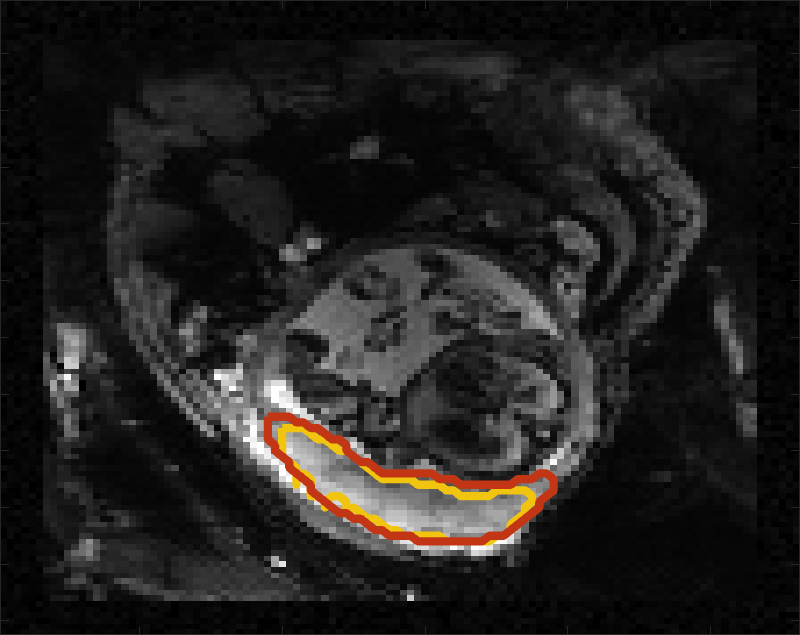

Despite its importance for many downstream clinical research tasks, placental segmentation is often performed manually and can take a significant amount of time, even for a trained expert. For BOLD MRI studies, manual segmentation is rendered more challenging due to the sheer number of MRI scans acquired and rapid signal changes due to the experimental design. Experiments acquire several hundred whole-uterus MRI scans to observe signal changes in three stages: i) normoxic (baseline), ii) hyperoxic, and iii) return to normoxic. During the hyperoxic stage, the BOLD signals increase rapidly, leading to hyperintensity throughout the placenta. Furthermore, the placental shape can undergo large deformation caused by maternal breathing, contractions, and fetal motion which can be particularly increased during hyperoxia [25]. See Fig. 1 for two examples.

Fig 3 compares the predicted label maps with ground truth on subjects with increasing Dice scores using the BW-CE model. The model accurately identifies the location of the placenta, but in the worst cases misses boundary details.